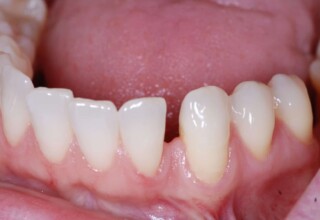

Αποκατάσταση Οπίσθιου Απονευρωμένου Δοντιού με Ανασύσταση Σύνθετης Ρητίνης

Η συνήθης αποκατάσταση ενός απονευρωμένου οπισθίου δοντιού είναι με μια στεφάνη. Ο κύριος λόγος είναι η προληπτική προστασία από κάταγμα και την επακόλουθη εξαγωγή. Σε πολύ συγκεκριμένες περιπτώσεις όπου εξειδικευμένα κριτήρια (κυρίως η ποσότητα της εναπομείνουσας οδοντικής ουσίας) ικανοποιούνται ή όταν η οικονομική δυνατότητα του ασθενή το επιβάλει, μια εκτεταμένη ανασύσταση συνθέτης ρητίνης μπορεί ν’αποκαταστήσει την αισθητική και λειτουργικότητα του δοντιού.